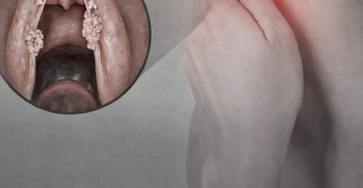

Quels sont les symptômes d’une infection au VPH au niveau de la gorge ?… En savoir plus

Cancer du pharynx (1/10) La célèbre chanteuse française Françoise Hardy est décédée le 11 juin 2024, à l’âge de 80…